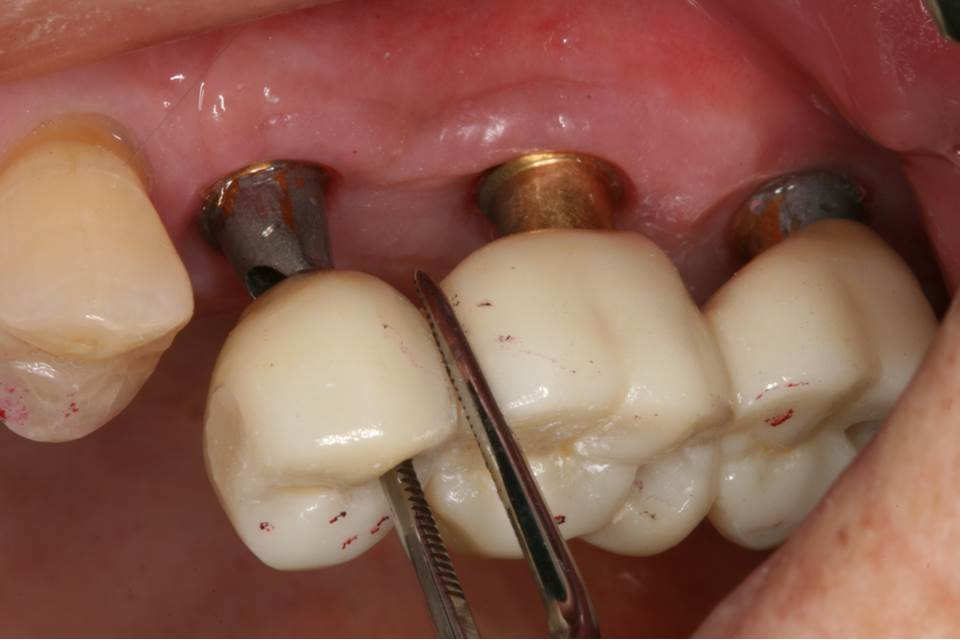

Monolithic zirconia restorations were fabricated for final prosthesis.

Stock abutments were milled to fabricate cement-retained prosthesis.

The final prosthesis (splinted monolithic zirconia crowns) was delivered after contact and occlusal adjustments.